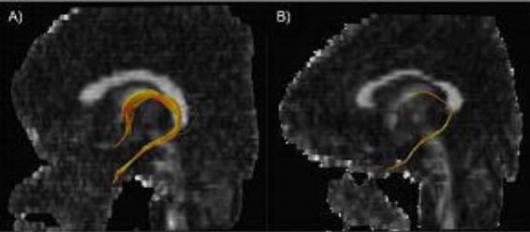

일반인의 뇌(왼쪽)와 대구 지하철 참사 생존… 일반인의 뇌(왼쪽)와 대구 지하철 참사 생존자의 손상된 뇌를 단층 촬영한 사진.생존자의 영상에서는 공포와 감정을 조절하는 신경회로(노란색)가 일반인에 비해 3분의1 수준으로 수축돼 있다.

서울대병원 신경정신과 류인균 교수는 20일 “지난해 11월부터 3개월 동안 외상후 스트레스 장애를 겪고 있는 당시 생존자 20여명의 뇌를 단층촬영한 결과 감정과 공포를 조절하는 신경 부분이 일반인에 비해 심하게 손상된 사실을 확인했다.”고 밝혔다. 실제 류 교수가 공개한 생존자들의 뇌 단층촬영 화면에서는 감정과 공포를 조절하고 문제해결 능력을 관장하는 대뇌의 전두엽과 측두엽 부분이 심하게 훼손된 것으로 나타났다. 이에 따라 생존자들은 작은 충격이나 공포에도 심하게 놀라거나 외부 자극에 반응을 제때 하지 못하고 멍해지는 현상을 보인다는 것이다. 또 이들의 뇌세포 수나 크기가 줄어 밀도가 낮았으며, 뇌에 공급되는 피와 산소량도 특정 부위에서는 일반인보다 많고, 다른 부위에서는 적은 이상 현상이 확인됐다. 이같은 혈류량의 이상은 감정조절과 언어능력, 촉각·시각·청각 등 감각능력을 떨어뜨리게 된다.